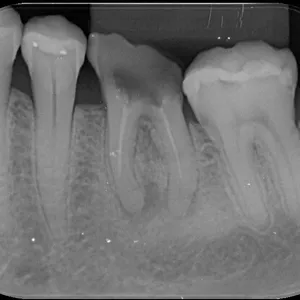

Sabemos que o exame clínico é soberano, mas não podemos deixar de dar a devida importância aos exames complementares que tanto nos auxiliam no diagnóstico preciso do caso.

Esse é um modelo de solicitação de exame radiográfico perfeito para você baixar, usa e abusar.

Lembre sempre que o cirurgião dentista tem total autonomia na solicitação de exames complementares e deve detalhar e indicar o motivo específico do exame solicitado.